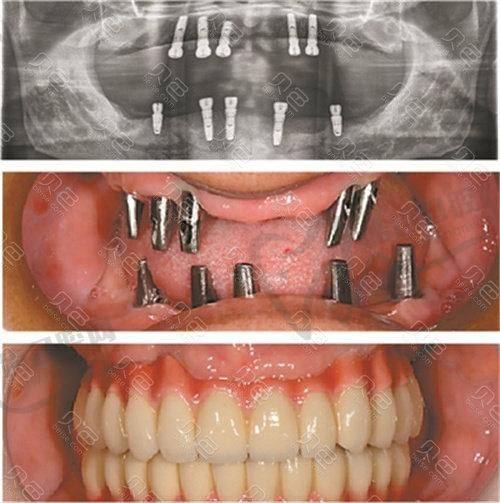

技术优势:医院拥有精良的口腔诊疗设备,如口腔显微镜、数字化口腔扫描仪等,为种植手术提供精细的诊断和治疗。医生团队由多名经验多的口腔骨干医生组成,他们在种植满口牙方面有着丰富的临床经验和独特的技术优势。采用精良的种植技术,如即刻种植、all-on-4种植等,缩短患者的治疗周期,提高患者的生活质量。